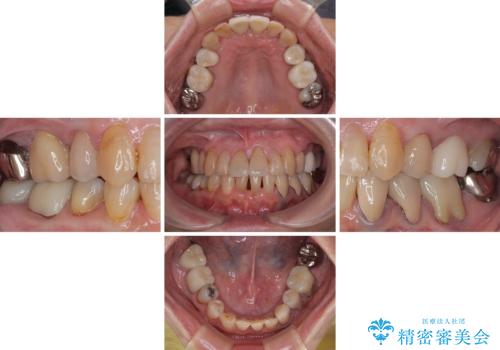

長年気になっていた前歯 矯正治療と補綴治療による審美歯科治療

- 長年気にしていた捻れた前歯が欠けたとのことで来院された患者様です。

矯正治療に抵抗があったそうですが、前歯が欠けたことをきっかけに、矯正治療で歯列を整えた上で、セラミッククラウン治療を行う決心が付いたとのことでした。

デコボコが強いため、ブリッジや残根となっている部分のスペースを利用して歯列を整え、変色や欠けている歯をオールセラミッククラウンによる補綴治療を行うこととしました。